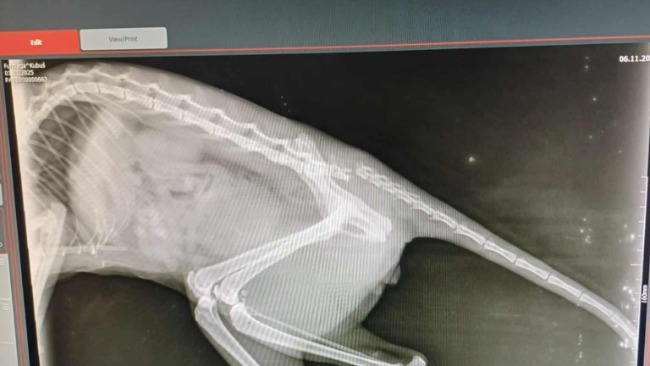

Nie jesteśmy kocią fundacją, nie mamy kociarni, ale nie odmawiamy pomocy kotom, gdy ich stan jest tragiczny. O taką pomoc poprosiły Dorota I Ania dla kota po wypadku. Tylko one zauważyły leżącego na ulicy kota w tragicznym stanie. Badania wykazały złamany ogon tuż przy kręgosłupie oraz złamany kieł, co sprawiło, że z bólu kot nie mógł jeść.